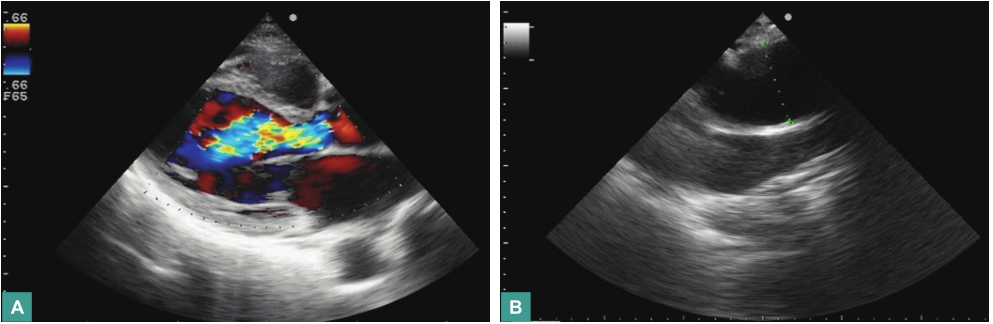

心脏超声(2011年8月29日)示主动脉扩张伴主动脉瓣反流(++++),左心房、左心室扩大伴二尖瓣反流(++~+++),右心房扩大,三尖瓣反流(++~+++);射血分数(EF)53%(图2);胸主动脉CTA示升主动脉及主动脉弓扩张(内径约5.4cm)(图3)。

图2 心脏超声(2011-08)

图3 心脏超声(2011-08)